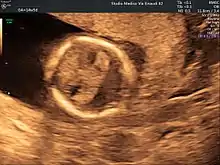

Holoprosencephaly is typically diagnosed during fetal development when there are abnormalities found on fetal brain imaging, however it can also be diagnosed after birth. The Protocol for diagnosis includes neuroimaging (Ultrasound or fetal MRI prior to birth or Ultrasound, MRI or CT post birth), syndrome evaluation, cytogenetics, molecular testing, and genetic counseling.[3]